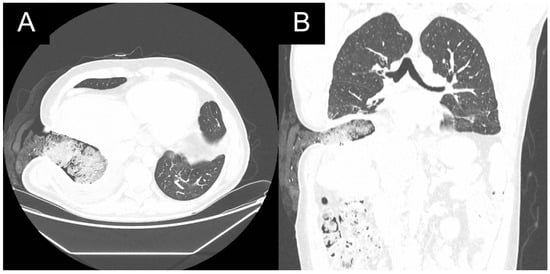

In the presented case, the hepatic lesion ruptured directly to the right lower segmental bronchus S10 as confirmed acutely in a flexible bronchofibersocopy, where large amounts of purulent discharge were lavaged. Chest CT showed communication of the ruptured lesion with the large right airways (Figure 5). This acute respiratory situation required an urgent surgical procedure. The presence of pneumonitis precludes parenchymal resections. A thoracotomy for exploration and meticulous debridement was followed by formation of an open fenestration at the level of the 9th rib to control infection without parenchymal resection (Figure 6). Regular dressing changes and long-term anthelminthics controlled the infection (Figure 7).

Figure 7. Postoperative chest CT in (A): axial and (B): coronal views of patient 1 with open window thoracostomy.